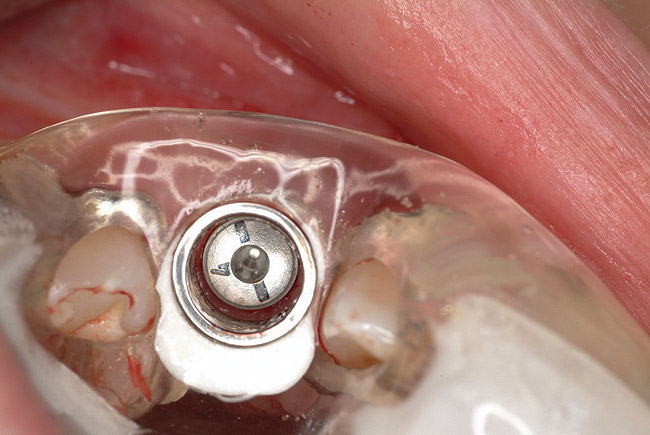

Figure 8  Primary stability of the implant achieved, facilitating a transmucosal healing approach.

Figure 8

Figure 9  Primary stability of the implant achieved, facilitating a transmucosal healing approach.

Figure 9

Approximately 4 months after grafting, the patient returned for clinical and 3-D radiographic evaluation. The thinnest area of ridge width preoperatively was remeasured in approximately the same location, demonstrating a gain of about 4 mm (Figure 7). The treatment plan was to place a 3.5-mm x 13-mm implant with a computer-generated guide (SiCat, Sirona Dental, www.sironausa.com), eliminating an additional open surgical procedure. Planning included initial osteotomy preparation with single-use drills combined with a localized ridge expansion using narrow, tapered osteotomes. This was performed approximately 5 months after the augmentation procedure, achieving primary stability of the implant, facilitating a transmucosal healing approach (Figure 8 and Figure 9). Following each step of osteotomy preparation, a probe was inserted along the walls of the site to confirm the integrity of the buccal and palatal walls prior to implant insertion.